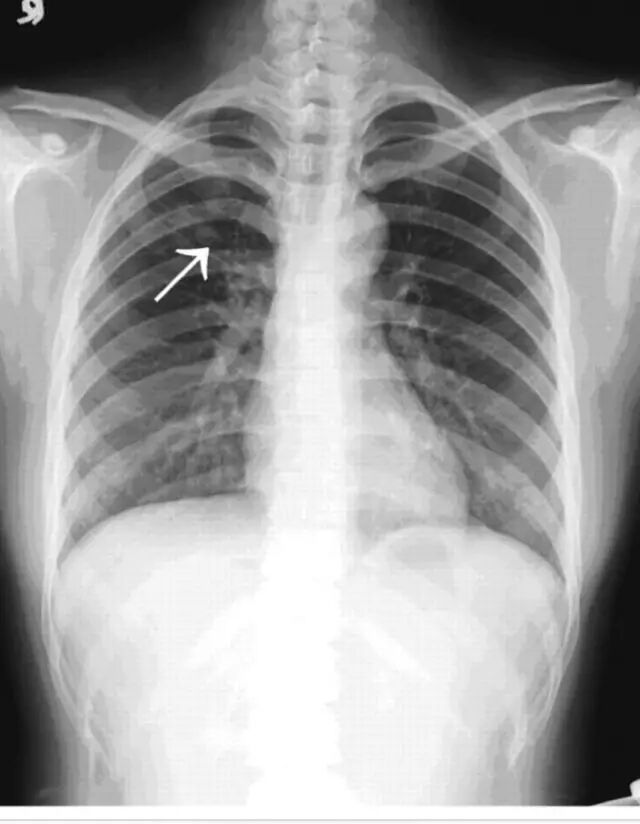

方先生的主诉是咳血。十个多月前,出现痰中带血,晨起时尤甚。痰量并不大,但却总掺着暗红色血丝。去看病的第一次,简单的x光胸部平片上就已可以看出病情的严重。他的右上肺有一大片阴影,边缘鼓起多个棘突,中央区域已经开始形成空洞。这样的症状与影像表现加在一起,就连外行的病人自己也意识到,首先怀疑的就是肺部肿瘤,而且恶性的可能性极大。